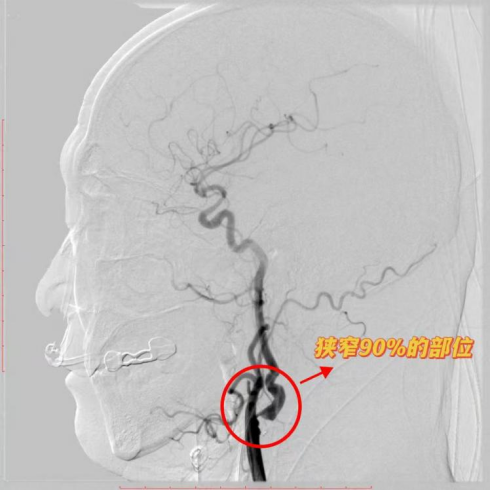

近日,济南南郊医院脑科团队成功为一名61岁男性患者实施高难度颈动脉内膜斑块切除术,帮助患者摆脱脑卒中高风险威胁。该患者有高血压病史,超声筛查发现右侧颈动脉重度狭窄(达90%),且斑块呈低回声特征——这往往提示为易脱落的不稳定斑块。术前造影进一步显示,斑块负荷量大,且远端血管存在明显迂曲,手术难度极高。

面对复杂病情,北医三院神经外科专家尹晓亮教授与济南南郊医院郭晓宾主任团队展开联合会诊。考虑到患者斑块不稳定、远端血管迂曲,若采用支架成形术,球囊扩张可能导致斑块脱落引发脑梗。经与家属充分沟通,最终选择更稳妥的颈动脉内膜斑块切除术手术方案。术中,专家团队凭借精湛技术,精准剥离高负荷不稳定斑块,同时巧妙处理迂曲血管,全程严密防控栓塞风险。术后,脑科团队对患者进行全天候生命体征监测及个性化康复指导,目前患者各项指标平稳,恢复良好。